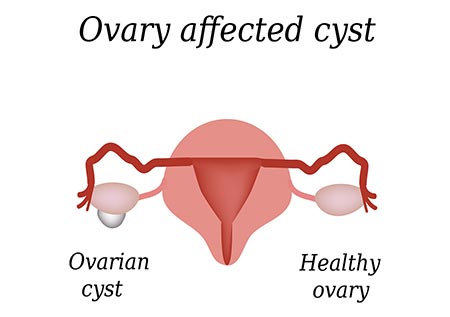

انواع کیست تخمدان و روش های درمان آن

تخمدانها چگونه کار میکنند؟ تخمدانها دو اندام کوچک و لوبیا شکل هستند که بخشی از سیستم تولید مثل هستند. یک خانم دو تخمدان دارد- هر یک از تخمدان ها در یک طرف رحم قرار دارند. تخمدان دو وظیفه اصلی دارد: – هر 28 روز تخمک را به عنوان بخشی از چرخه قاعدگی آزاد می کند – هورمون های زنانه، استروژن …